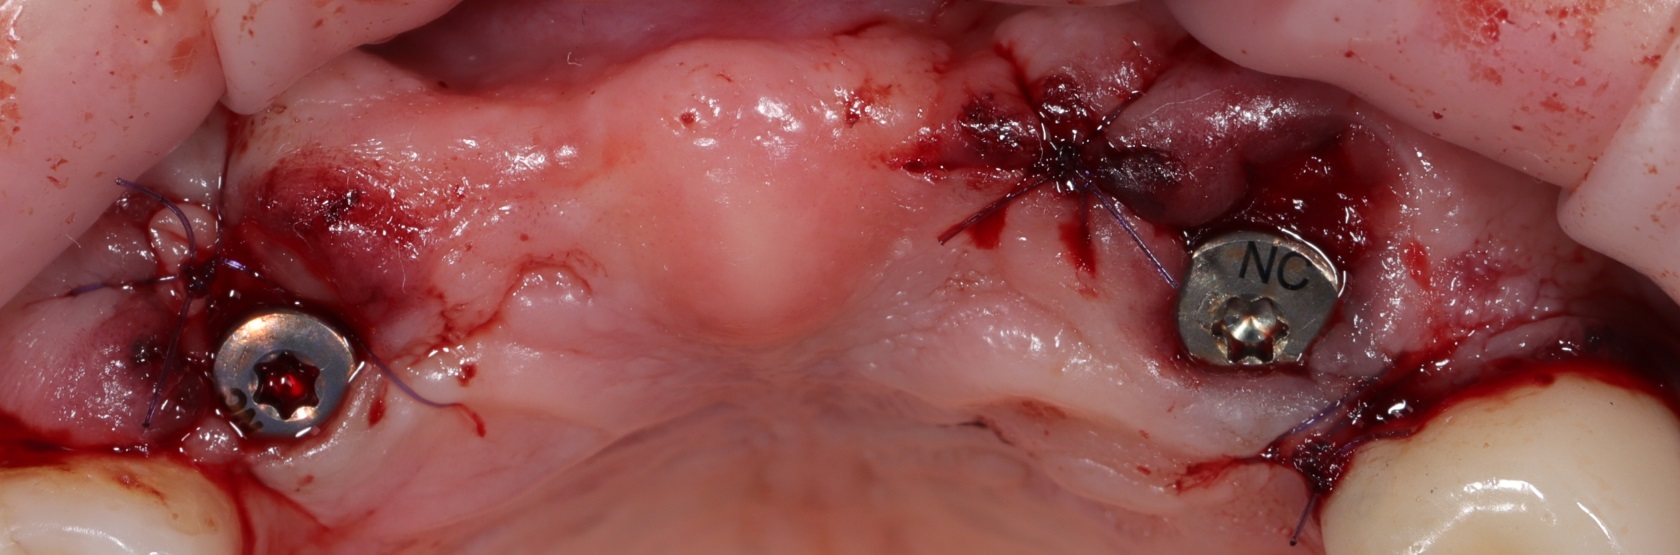

Спустя три месяца мы получили полное восстановление костной ткани. Мы установили 4 импланта в позиции 13, 14, 16, 17. Сразу были установлены формирователи десны.

Спустя три месяца вы видим отличный результат как на рентген снимке, так и на фото. Объема слизистой достаточно для начала ортопедического этапа.